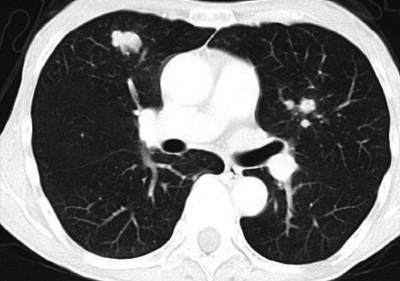

尿所見:蛋白(-)、糖(-)、沈渣に赤血球1〜5/1視野、白血球1〜5/1視野。血液所見:赤血球 420 万、Hb 12.8 g/dL、Ht 41 %、白血球 3,900、血小板 17 万。血液生化学所見:総蛋白 7.0 g/dL、アルブミン 3.8 g/dL、総ビリルビン 1.1 mg/dL、AST 34 U/L、ALT 36 U/L、LD 176 U/L(基準 176〜353)、γ-GTP 38 U/L(基準8〜50)、 尿素窒素 20 mg/dL、クレアチニン 1.0 mg/dL、尿酸 7.1 mg/dL、血糖 96 mg/dL、Na 137 mEq/L、K3.9 mEq/L、Cl 104 mEq/L。CRP 0.1 mg/dL。心電図に異常を認めない。11 か月前と今回の胸部CTを示す。

11か月前